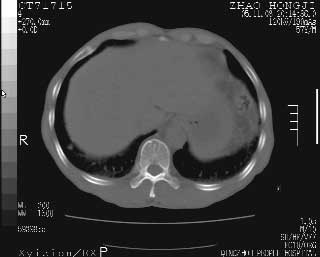

临床资料:男性,57岁,上腹部疼痛并5天,突然加重并延及全腹伴恶心5小时入院。胰淀粉酶化验在正常范围。检查:腹肌紧张,全腹压痛、反跳痛,尤以右上腹部为著。肠鸣音减低。血常规:wbc14.6x10/9, n:11.3x10/9 ,血压:135/90mmhg. 胸部透视:腹部肠腔轻度张气,未见其它异常改变。

肝右前缘少量积气,其他未见明显异常.考虑上消化道穿孔.

小网膜囊积气液,胃壁僵硬。考虑胃穿孔。

小膜网膜积液,肝缘气腹征,上消化道穿孔。

胰腺形态规则,胰周脂肪间隙清晰,结合临床可排除急性胰腺炎

从图提示我同意空腔脏器穿孔的诊断,来源肠道{由于病程较短,故没能见到肠系膜聚局的征象}。

肝缘见少许气体,胰尾部见少许气体包饶(蓝色圈),12指肠上部或球部邻近胆囊周边也可见少许气体影(黄色圈),并忖托出胆囊壁,12指肠远段肠道内未见明显气体(白色箭)。

肝脏前缘见少量积气、胰尾部见少许气体包饶,肾前筋膜未见增厚,临床淀粉酶不高,意见:上消化道穿孔。

消化道穿孔。12指肠球部周和胰周积气考虑12指肠穿孔可能性大。

入院3小时后行剖腹探查术,见腹腔内大量脓性混浊液约1000ml,十二指肠球部溃疡穿孔,溃疡面约2.5x2cm,穿孔直径约0.6cm。胃内容物外益,周围组织炎性水肿明显。行十二指肠穿孔修补术。术后诊断:

1、十二指肠溃疡穿孔

2、弥漫性腹膜炎

对于少量的腹腔游离气体,ct检查较普通透视有绝对的优势,它不仅可以看到肝脏前上缘的气体,而且还能够看到小网膜区的游离气体。从而可以肯定诊断。各位分析战友的很好,感谢大家的参入!